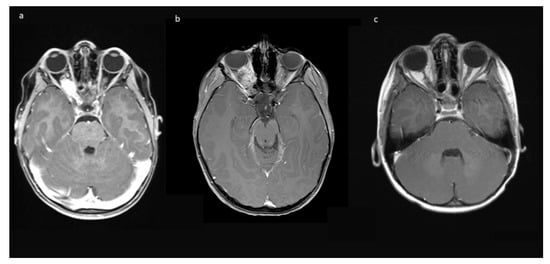

Indications for surgery were blindness/non-serviceable vision of the affected eye, disfiguring exophthalmos, pain, and documented tumor growth. A combination of factors was often present. All preoperative MRIs showed contrast-enhancing tumor growth from the orbit into the optic canal, and in 8/10, further intradural tumor extension affecting the ipsilateral optic nerve but not the optic chiasm (Figure 1).

Figure 1. Exemplary MR-imaging of a 3-year-old male (a) preoperatively, (b) 1 month postoperatively, and (c) 2 years postoperatively.